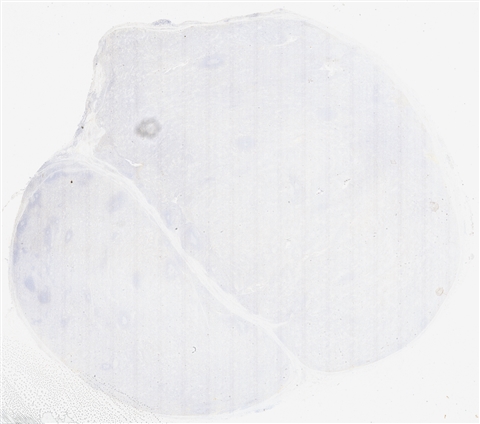

案例5 (6864)

性别:       年龄:62

患者详情: 发现双侧腹股沟肿物1月余。 查体: 双侧腹股沟可扪及多发肿大皮下肿物,大小约2*2cm,质中,边界尚清楚,活动度可,伴压痛,表面皮肤未见红肿破溃。 B超: 双侧腹股沟淋巴结肿大。 病理检查:腹股沟淋巴结穿刺活检提示淋巴组织增生。随行左侧腹股沟淋巴结切除术。

大体所见: 结节状肿物1枚,大小3×2×1.5cm,表面附有包膜,切面灰白灰红色,实性,质中。

医院: 上海长海医院